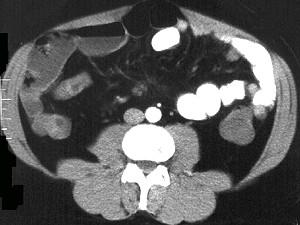

问题 女,30岁,右下腹痛,腹泻便秘交替出现,消瘦乏力,血沉加快,X线检查如图,最佳的诊断是 ( )

选项 A、结肠癌 B、阑尾炎 C、小肠结核 D、小肠克罗恩病 E、小肠癌

答案 D